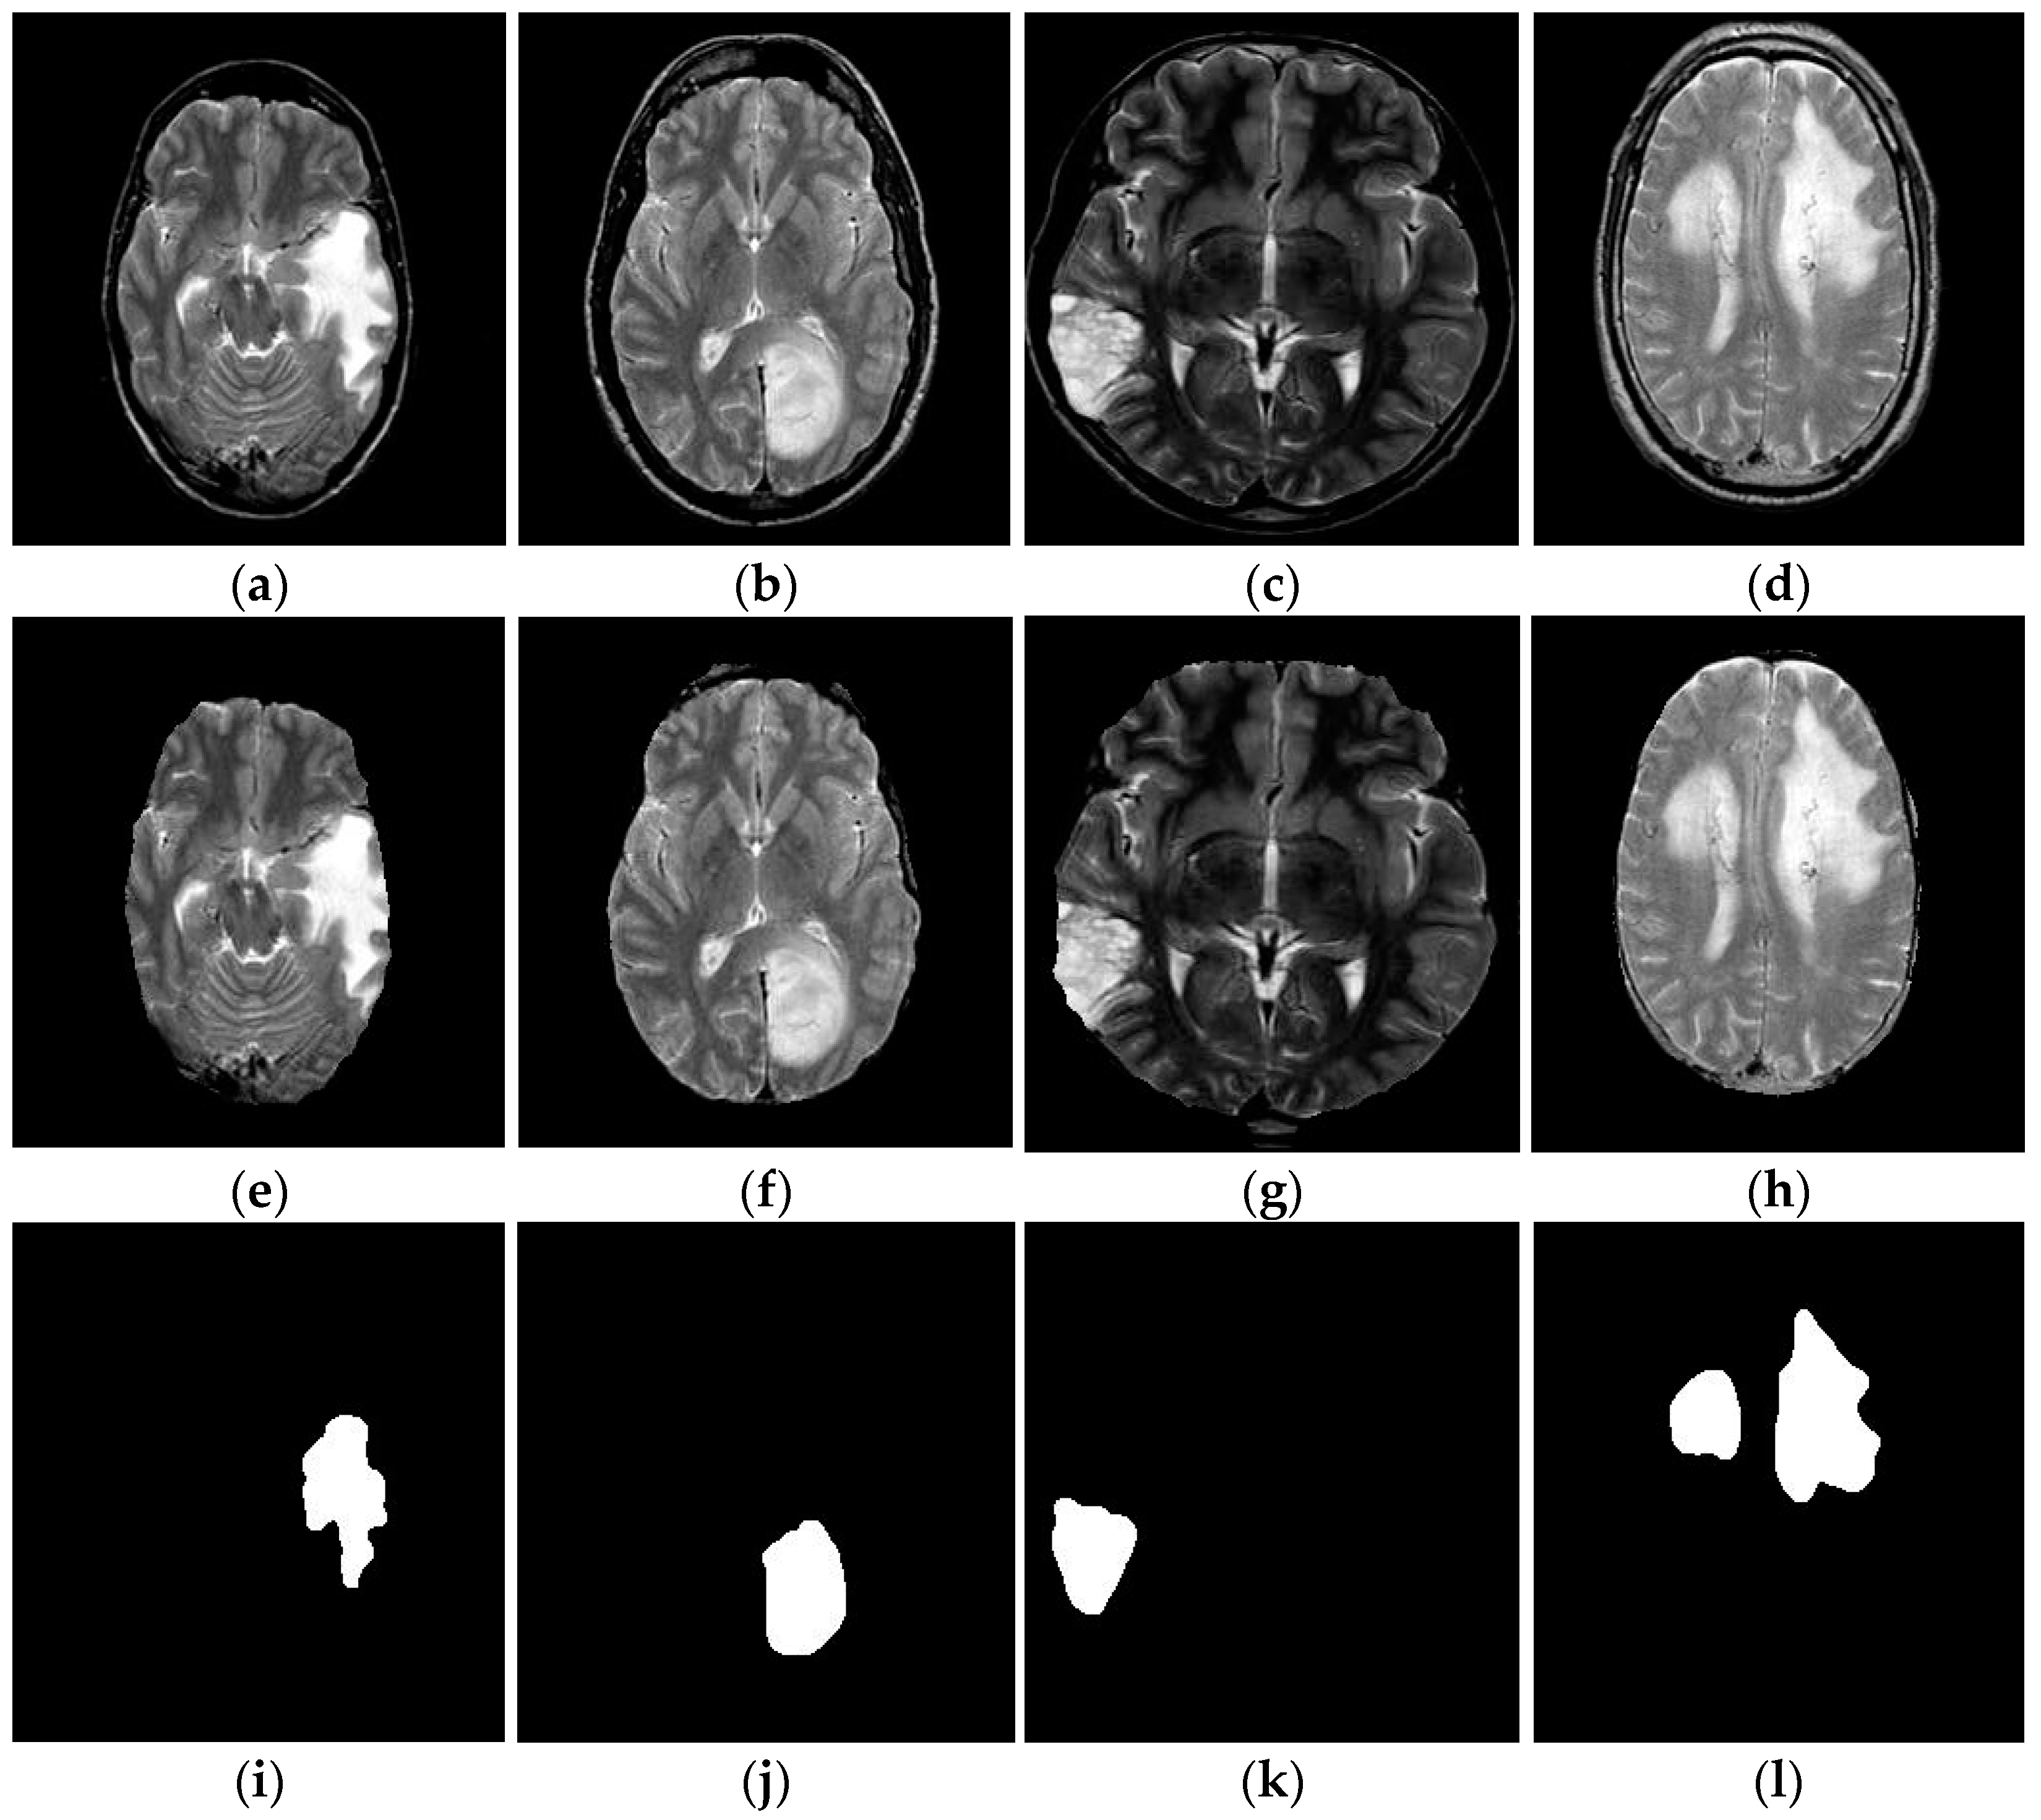

4.1.2. Segmentation Analysis

- Using the proposed skull-stripping process, we significantly isolate the brain tissues from non-brain matters. Due to this, the implemented approach accurately identifies brain-related diseases.

- The proposed FL-MSCM makes each region as homogeneous as possible, with high computational efficiency, simple parameter tuning, low reduction in contrast, and image details. It is a significant advantage of the FL-MSCM.

- The implemented approach access adequately visible edges or boundaries.